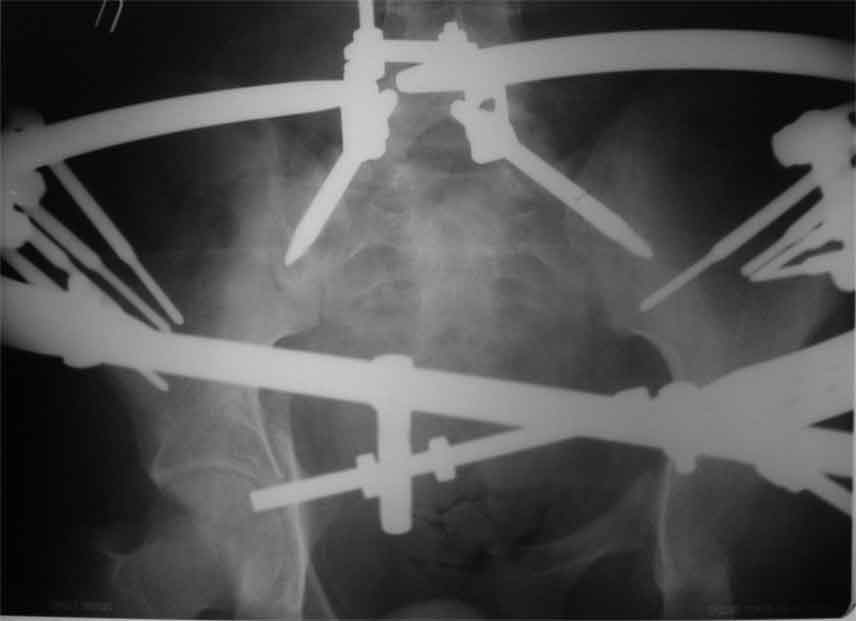

продолжение темы. не увидел энтузиазма в обсуждении. Вопросы прежние, первым этапом закрыто устранили вертикальное и передне-заднее смещение. Каким образом восстановить целостность тазового кольца, из каких доступов? Снимки в приложении

передне-неружным внебрюшинным доступом к лонно-седалищномц сочленению - синтез штангами(можно из заднего доступа, но хуже обзор и труднее репозиция), из этого же доступа к крыше вертлужной впадины - синтез реконструктивными пластинами(мы делали "ChM" тазовыми, хорошо себя зарекомендовали), передним доступом на лонное сочленение - синтез подобной пластиной. к задней колонне вертлужной впадины - задне-наружный доступ, синтез такой же пластиной. КРОВОПОТЕРЯ!!! возможно до 7л. мощная ангтибак. профилактика во время и после операции. до перехода на заднюю колонну оперировать в аппарате. бвл подобный случай, по снятии аппарата через 8 мес. - рецедив смещений сразу.